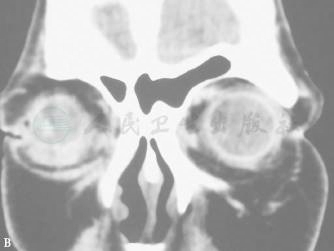

1.CT显示肿物呈囊性密度,边界清楚,多数无骨质改变,少数出现骨壁压迫改变(图4)。

图4 获得性结膜囊肿

A、B.冠状CT可见右眼球下方囊性密度影,边界清楚。